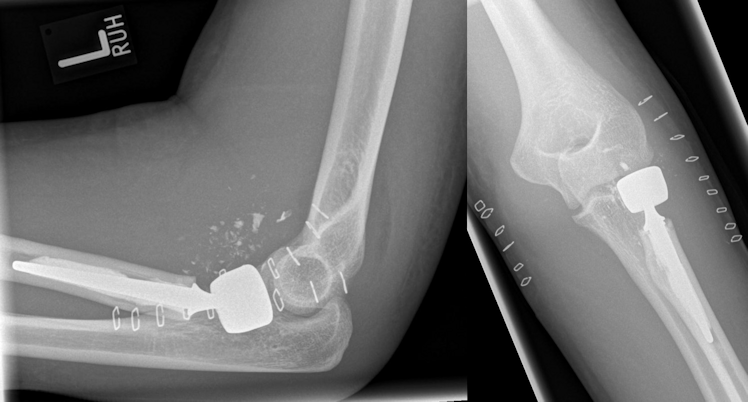

Figure 3: Postoperative radiographs after implantation of a cemented bipolar radial head prosthesis

Figure 4: Same patient 12 months after the injury: grade 1 degenerative changes and heterotopic ossifications at the elbow, but good to excellent functional results. No signs of loosening of the radial head prosthesis.